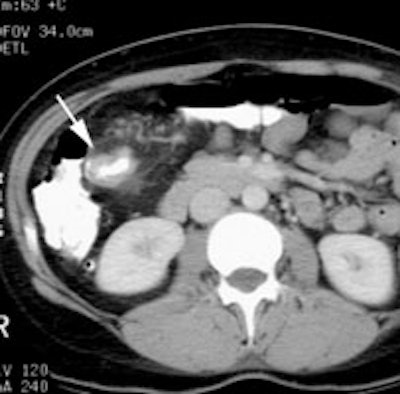

Initial staging for colorectal carcinoma: The patient below presented for evaluation of colorectal carcinoma. The CT scan demonstrated a large liver mass (red arrows) compatible with metastatic disease. The patient's cecal mass (black arrow on PET scan) was not detected on the CT study (white arrow). No other lesions were identified on the PET scan. |